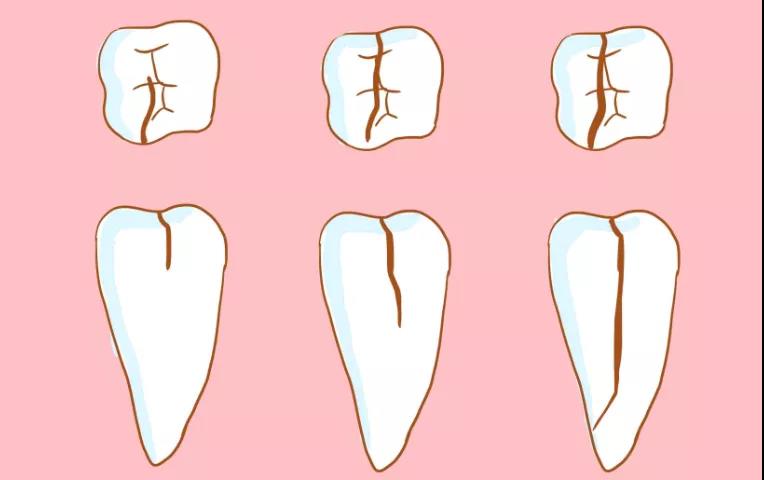

牙隐裂又称“不全牙裂”或“牙微裂”,是指牙冠表面出现非生理性的细小裂纹。

当牙齿因病理性磨损出现高陡牙尖时,吃东西会令牙尖压力增加,使窝沟底部的釉板向牙本质方向加深加宽,这就是隐裂纹的开始。

在力的继续作用下,裂纹逐渐向牙髓方向加深,从而形成了真正的牙齿隐裂。

病有轻重缓急,牙隐裂,也是一样。不同深度的裂纹,疼痛的感觉患病的严重性也不一样。